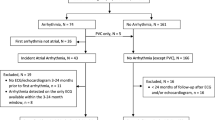

We performed AP measurements on RVOT samples from 25 patients with a mean age of 101 months (range 4 months to 56 years; Table S3). The underlying congenital heart defect was TOF in 22 and ASD in three patients. Six patients with TOF (median age 27 years) had previously undergone a repair operation (‘repaired patients’); all other patients (median age 10 months) had not previously received a repair operation (‘unrepaired patients’). All repaired patients demonstrated prolonged QRS durations in the pre-operative electrocardiogram, while all unrepaired patients had normal (age-adjusted) pre-operative QRS durations. Six patients experienced post-operative supraventricular or junctional arrhythmias, but none had ventricular arrhythmias or history of any kind of pre-operative tachyarrhythmia. For further clinical patient information, see Table 1 and Table S3.

Pro-arrhythmic electrophysiological tissue abnormalities

During AP recording, 4 of 12 (33%) samples from young (< 1 year) and 7 of 10 (70%) samples from older (≥ 1 year) patients with TOF showed either spontaneous or drug-induced arrhythmias. In the ASD group, 1 of 3 (33%) samples showed a drug-induced arrhythmia (Fig. 1, Table 1). There was no significant difference between tissue with drug-induced and tissue with spontaneous arrhythmias in RMP, dV/dtmax, APD20, APD50, APD90, and AUC90 of the non-arrhythmic AP over all pacing frequencies assessed (two-sample t-test, p > 0.05 for all). APA was slightly larger in tissue with drug-induced arrhythmias compared to tissue with spontaneous arrhythmias (two-sample t-test, p = 0.023).

Binomial logistic regression demonstrated a significant positive interaction of repaired status/QRS prolongation with tissue arrhythmias (t = − 2.0, p = 0.045), while there was no significant association of clinical arrhythmias with any clinical parameters or electrophysiological tissue abnormalities.